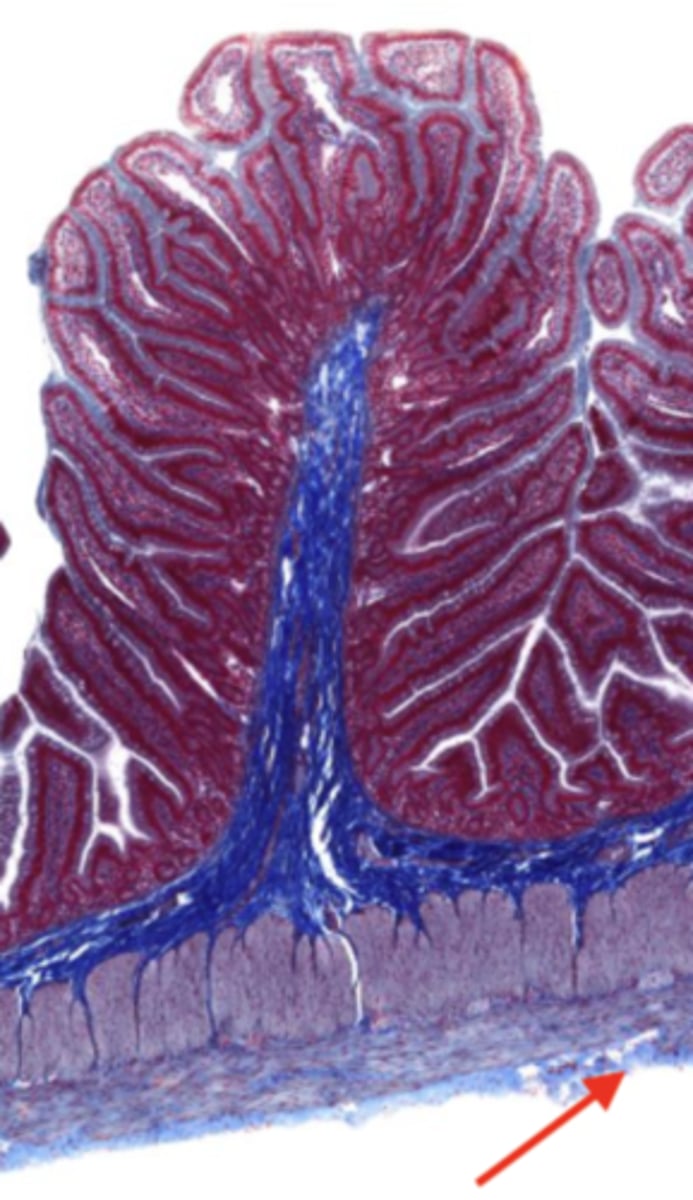

jejunum (histology)

villi (jejunum)

intestinal crypts (jejunum)

lumen (jejunum)

mucosa (jejunum)

mucosal epithelium (jejunum)

lamina propria (jejunum)

muscularis mucosa (jejunum)

submucosa (jejunum)

contains glands and blood supply

muscularis externa (jejunum)

serosa/adventitia (jejunum)